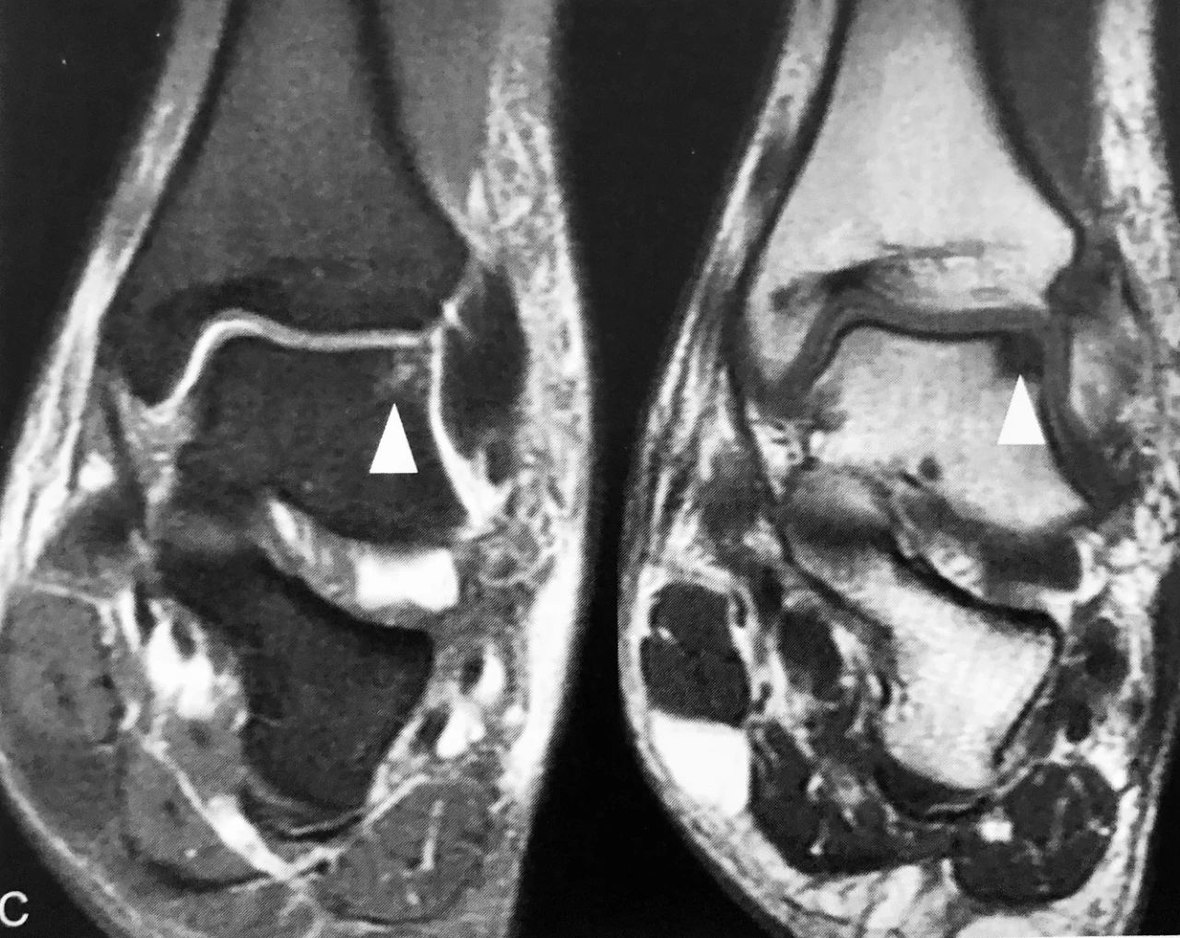

A~E.为同一踝关节外伤患者。A.Ⅹ 线侧位片见“泪滴征”(粗箭头),低密度前脂肪层受压移位变窄(细箭头),提示踝关节积液;B、D分别为踝关节积液MRI、CT表现(长箭头);C、E分别为距骨左份关节面下隐匿性骨折 MRI、CT 表现,MRI 示稍长 T2、长 T1信号,邻近距骨骨皮质连续性可疑中断(三角),CT 进一步明确距骨左份关节面下隐匿性骨折存在(三角)